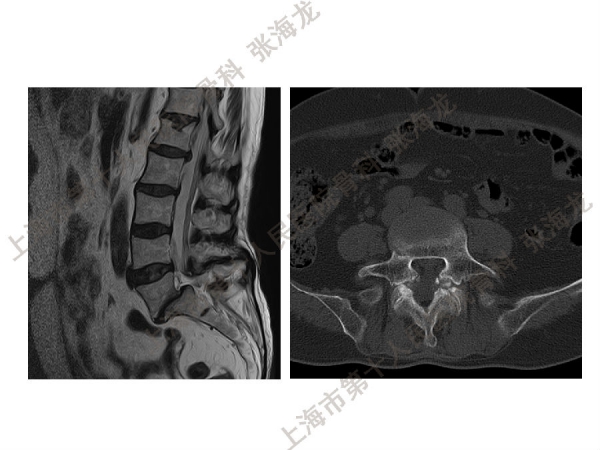

2008年3月至2010年8月,上海市第十人民医院骨科随访49例腰椎滑脱症(峡部裂型和退变型)患者,对比23例微创手术MIS-TLIF和26例开放手术治疗腰椎滑脱症的临床及影像学结果,进行了回顾性研究。

研究发现,Wiltse入路Mis-TLIF更直接的暴露峡部及关节突,对脊柱稳定性的影响较小;彻底松解辅助双重提拉复位Mis-TLIF,对于峡部裂型滑脱有较好的复位效果;对于峡部裂型滑脱,提拉复位在影像学参数上有一定优势;与原位融合相比,ODI.VAS.JOA无明显差异(样本量有限);对于退变性滑脱,单纯撑开椎间隙与原位融合可以获得较好疗效。